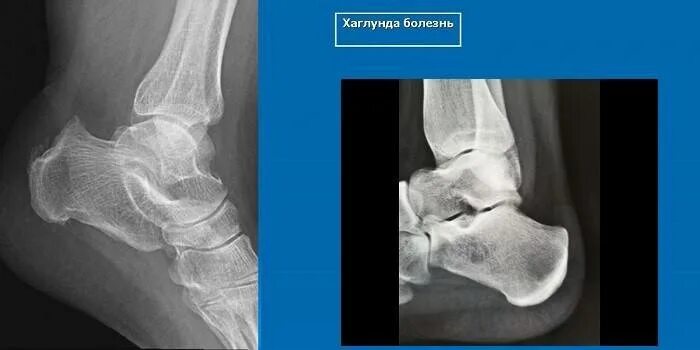

Болезнь шинца у детей код по мкб